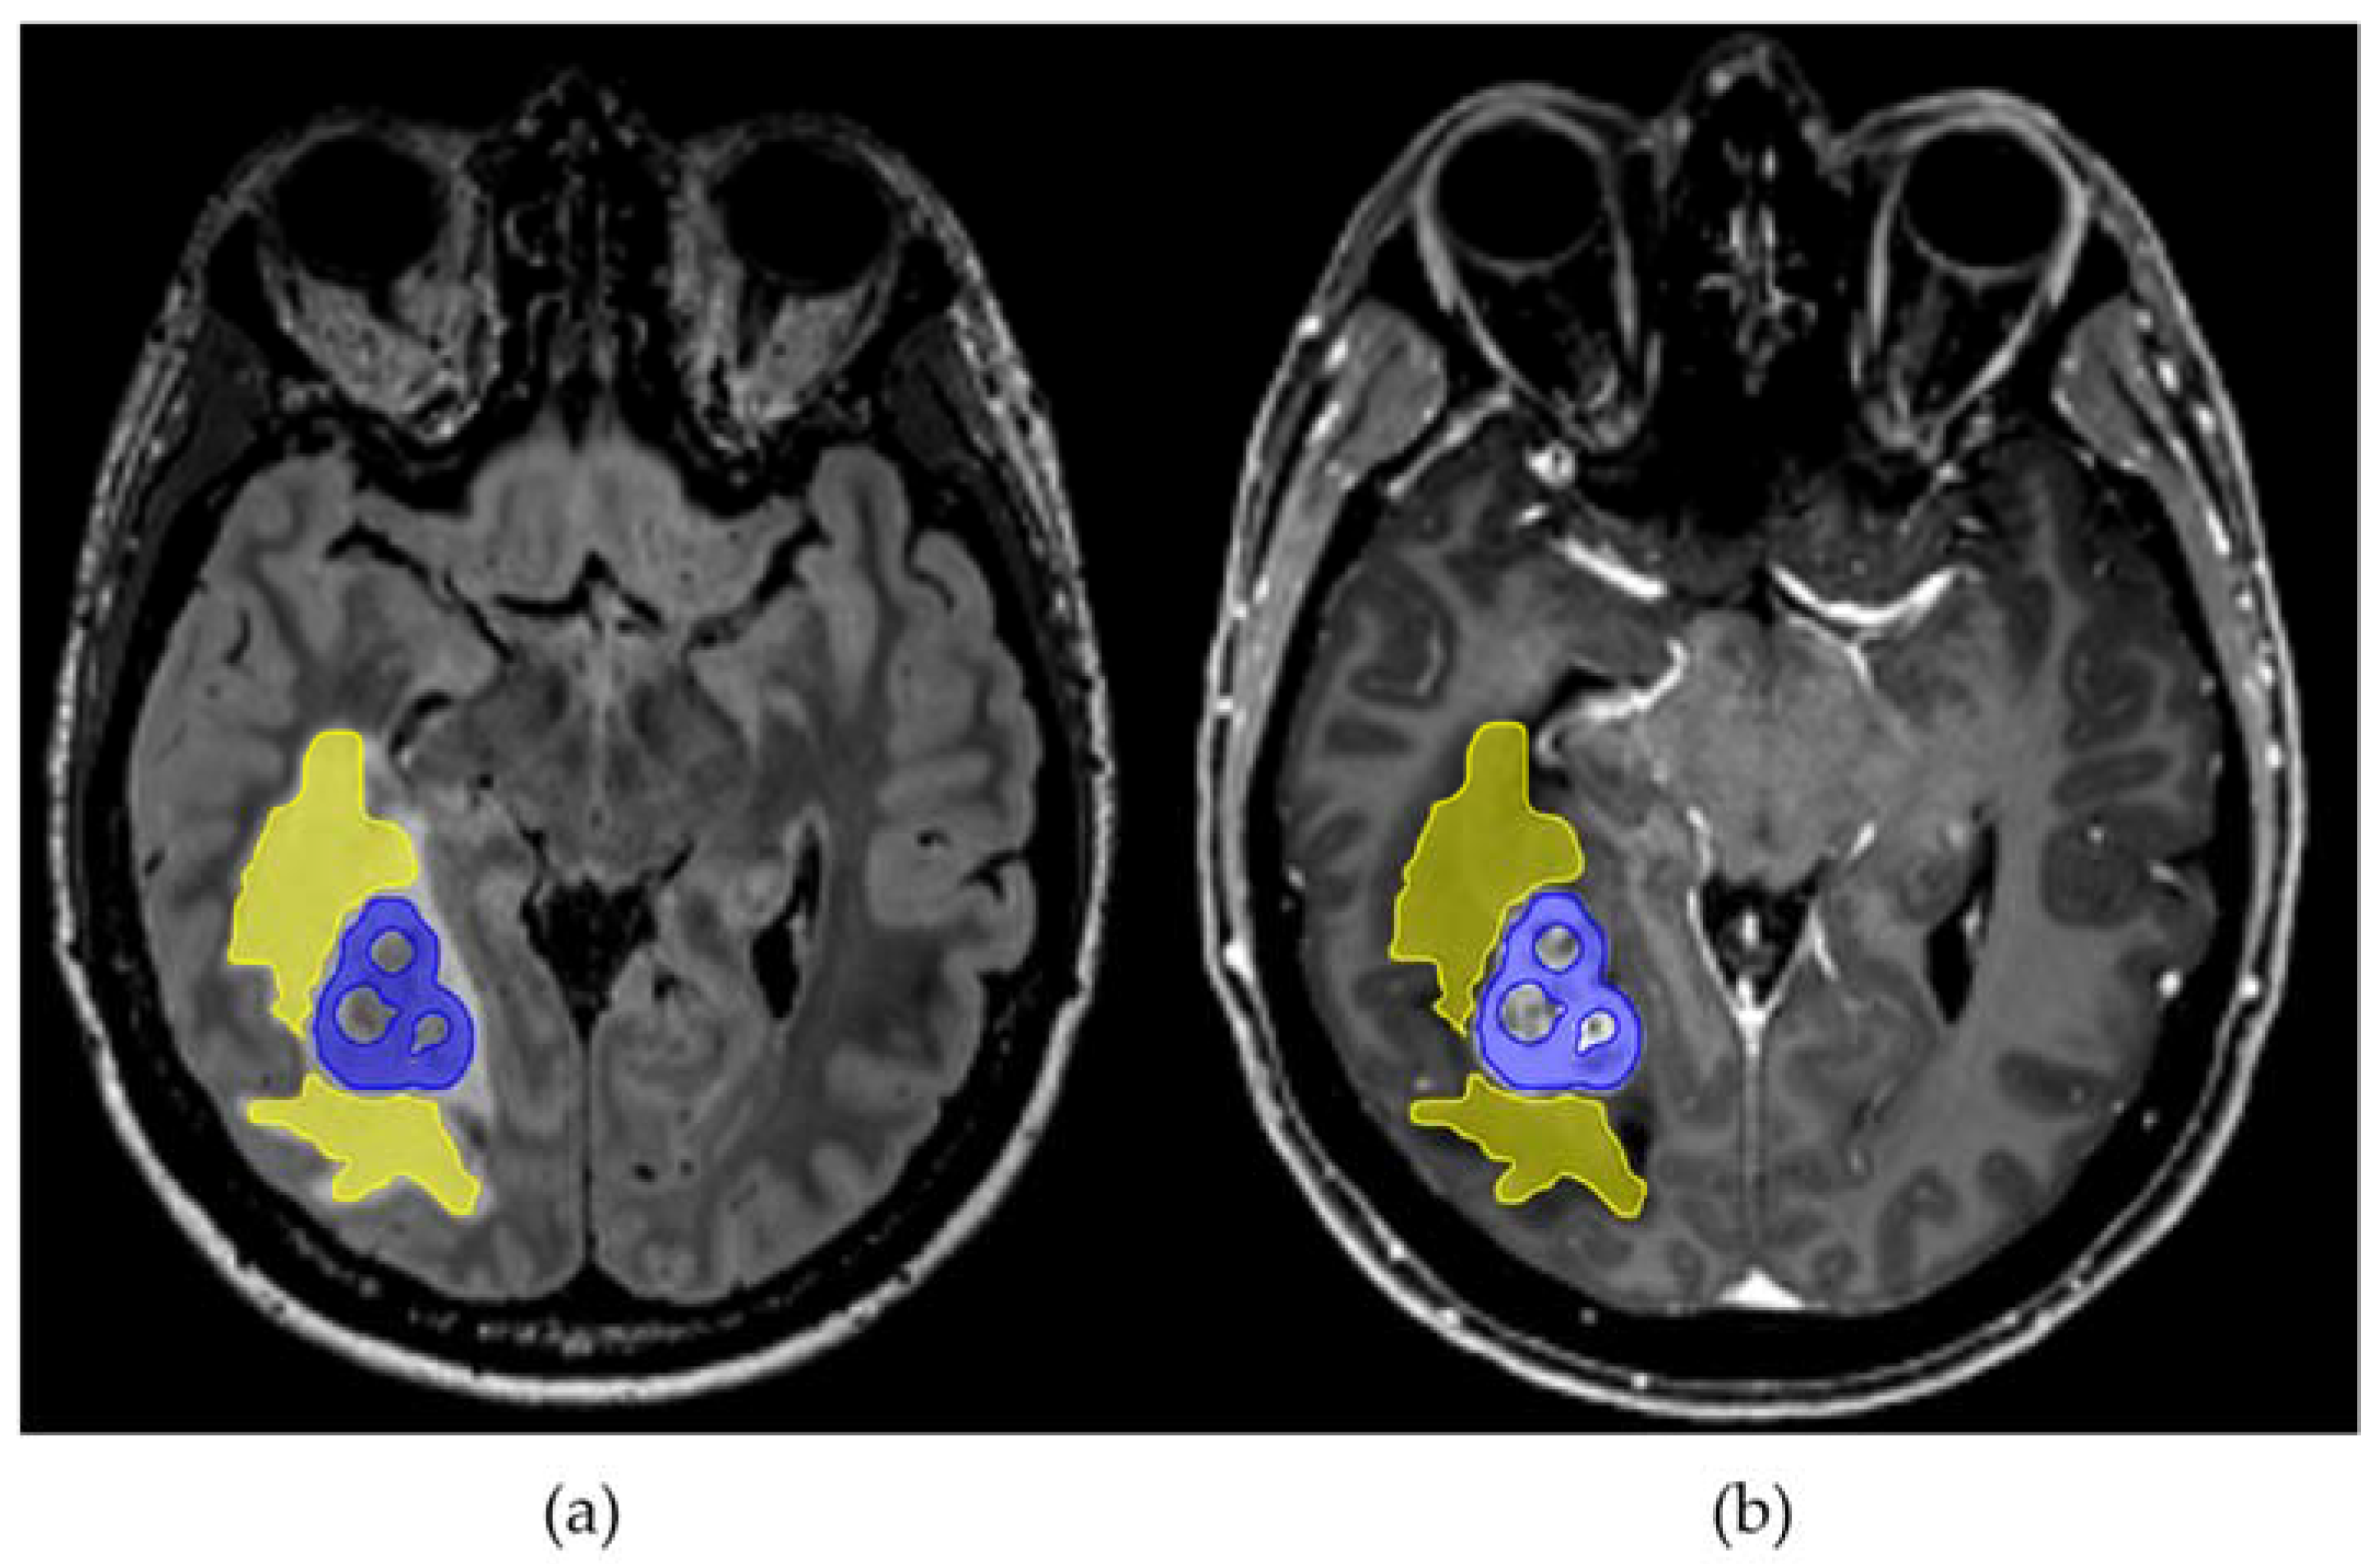

2.2. Diffusion Microstructure Imaging (DMI) and ROI Based Analysis